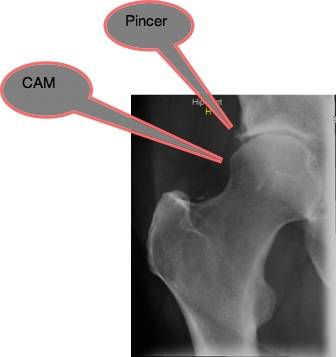

Femoro Acetabular Impingement Syndrome comes in two forms, which usually coexist.

The first, pincer, is a deformity of the acetabulum. The second, cam, is a growth on the neck of the femur.

In the xray above a CAM deformity is clearly seen. Below, closer inspection shows that he has in fact mixed CAM-Pincer deformity in this, his right hip; in fact in both. Moderate degenerative change is seen. An orthopaedic surgeon expects a bilateral hip replacement within two years.

In CAM there is an abnormality at the level of the anterior femoral head, or the head-neck junction, resulting in increased femoral neck/head - acetabular rim contact. Cartilaginous lesions form along either the postero-inferior or superior aspects of the acetabulum, causing stiffness and limiting the range of motion. A hard end-feel is characteristic.

In Pincer-Femero Acetabular Impingement Syndrome - the acetabulum gives increased coverage of the femoral head - femoral neck juntion, limiting the full range of motion of the hip. In particular, EXTERNAL ROTATION of the flexed hip is characteristic, again with a hard end-feel.